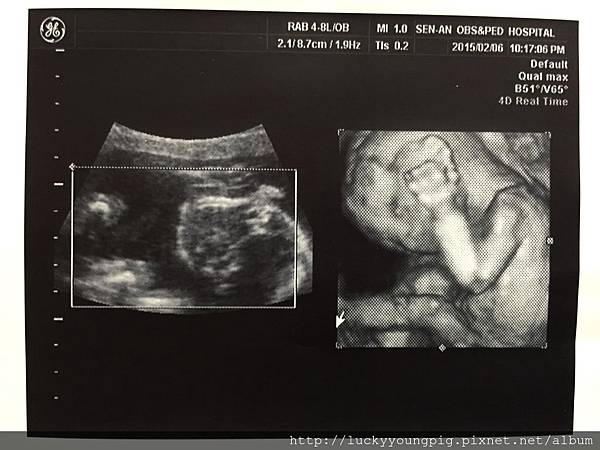

進了診間 醫生請我先照超音波 哇~太吸晴了

是4D的耶 這真的是滿足媽媽的眼慾 哈哈哈~

醫生照的非常仔細 也粉久

寶貝19w2d 頭圍腹圍大小正常 約300g哦~

醫生說 寶貝正在拉耳朵啦 哈哈哈~很調皮哦

醫生說 寶貝沒臍帶繞圍哦